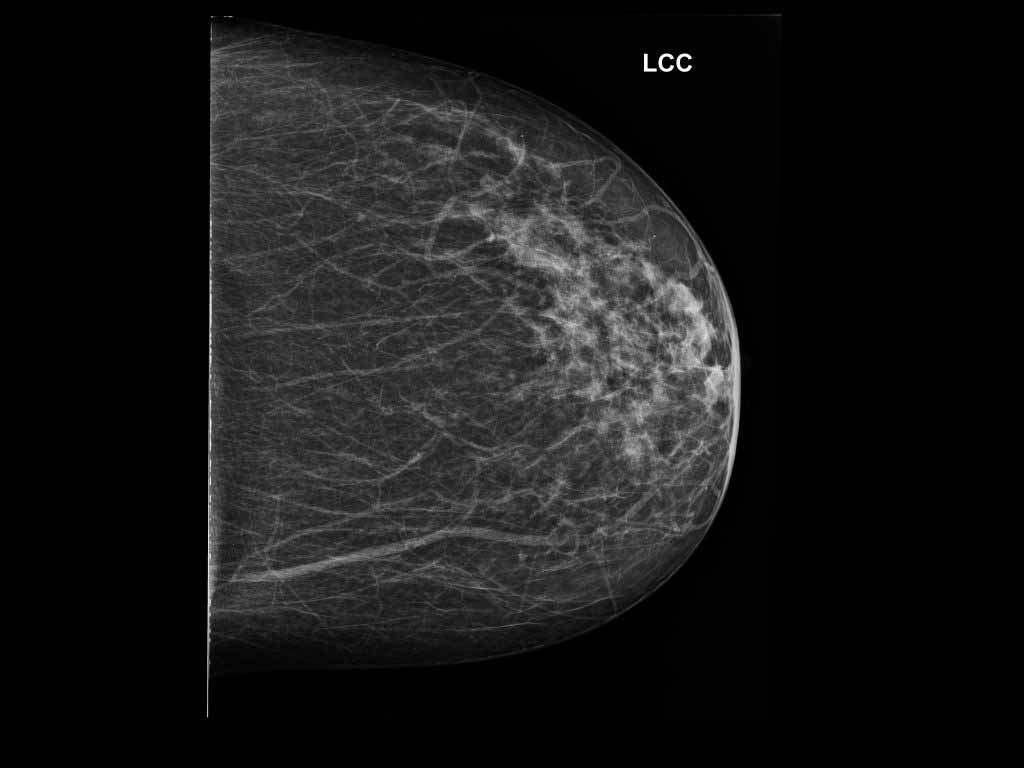

Kesesuaian Kategori Bi Rads Mamografi Dengan Pemeriksaan Histopatologi Di Rs Kanker Dharmais Tesis Pdf Download Gratis

Http Lib Ui Ac Id File File Digital 20367141 Sp Yulia 20rachmawati Pdf

Http Lib Ui Ac Id File File Digital 20367141 Sp Yulia 20rachmawati Pdf

Bab 2 Ca Mammae